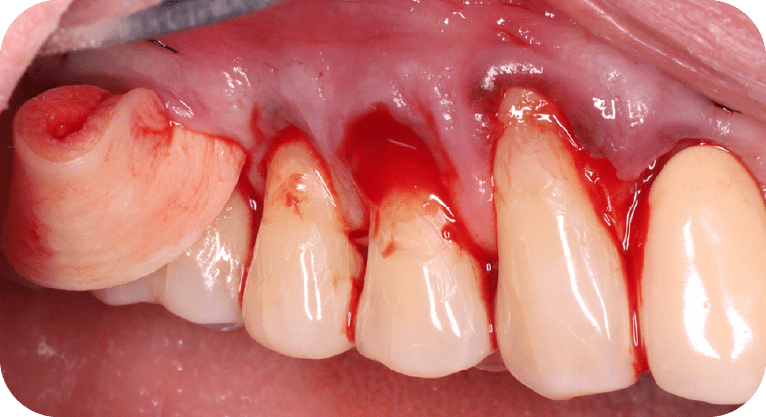

Male patient, “65” years old

Treatment: Gum surgery

The patient had dental sensitivity caused by exposed tooth roots, so a root coverage surgery with a gum gra and gum repositioning was performed. This procedure protected the exposed roots, reduced hypersensitivity, and improved both periodontal function and aesthetics, achieving satisfactory results for the patient.